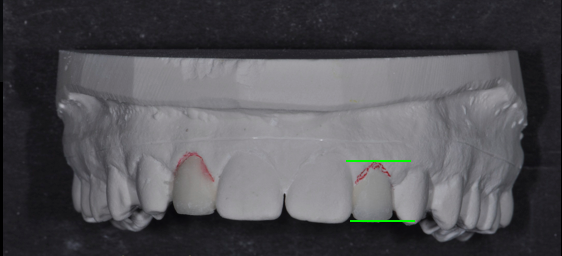

The guide’s most critical component is indicating the accurate gingival contour of the proposed final restoration. The surgeon uses this contour to visualize and measure implant-placement depth. The contouring is accomplished by fabricating a diagnostic wax-up.

The completed diagnostic wax-up must precisely outline the final gingival margin position, the position of the incisal edge and facial contour, and the embrasure form of the proposed restoration. The accuracy of these dimensions is essential for providing predictability to the outcome.

Once the diagnostic wax-up is designed, a duplicate model is fabricated. The simple surgical guide may be fabricated using a “suck down” technique using rigid, clear acrylic. The acrylic must be rigid enough to remain accurate for measurement during surgery and cold serializable. An ideal thickness to provide this accuracy is 1.5 mm. I commonly utilize 1.5 mm biocryl with a Ministar vacuum machine from Great Lakes Orthodontics.

Once fabricated, the acrylic guide may be trimmed with acrylic burs and discs to the desired gingival outline and contour.